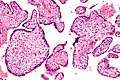

Intermed. mag.